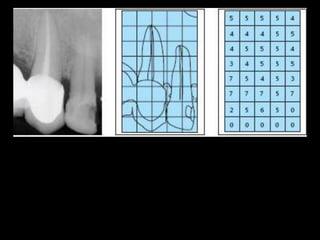

4. Digital radiography provides advantages like automated measurements and image manipulation but has higher initial costs and bulkier sensors.